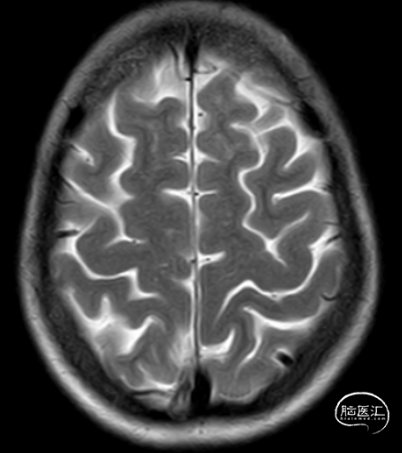

头颅MRI平扫

头颅MRI+MRA提示

1、右侧颈内动脉床凸段及眼动脉段动脉瘤?

6、脑白质病变。